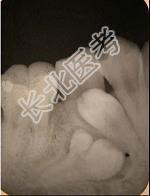

单项选择题融合牙是 ( )

D、两牙牙本质相连